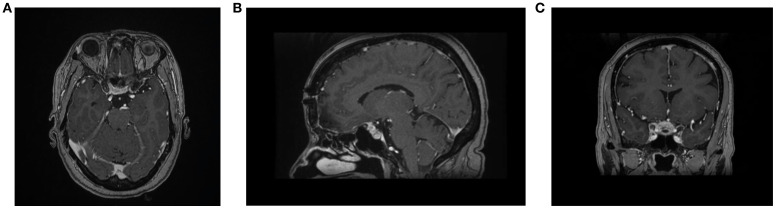

Tuberculum sellae meningioma (TSM) is an uncommon tumor among all intracranial meningiomas. As these tumors grow, they compress the surrounding structures, including the optic nerves and the pituitary gland. Ocular motor nerve palsy (OMNP) can occur as an isolated mononeuropathy or as part of multiple cranial nerve palsies. The role of corticosteroids in the management of OMNP has not been fully studied in the literature. In this report, we present a case of a previously well middle-aged woman who presented with severe headache and isolated OMNP on examination. MRI of the brain showed a small TSM that extends into the right optic canal. In our case, we noted the expedient and complete recovery of isolated OMNP within a few days following treatment with dexamethasone. This case report is on an isolated OMNP associated with TSM, which has not been previously reported. In addition, it highlights the role of corticosteroids in achieving rapid recovery from OMNP.